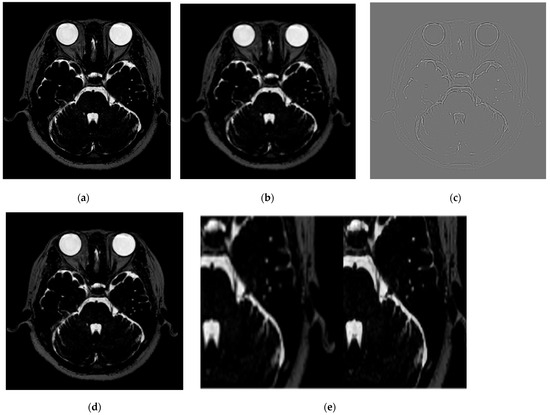

3.1. Improving the Image Quality of the Trigeminal Nerve